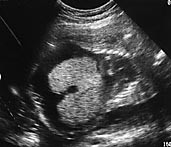

Etter enda ett år var kvinnen gravid på ny. Barnefaren var den samme. Hun ble henvist til Kvinneklinikken i svangerskapsuke 35 fordi fosteret var veksthemmet. Hun var i god allmenntilstand og hadde ikke tegn til preeklampsi. Hemoglobinverdien var 9,4 g/100 ml. Ultralydundersøkelse viste et veksthemmet foster ( −  25 %), lite fostervann og forstørret placenta. Fosterhjertet hadde fortykkede vegger og fylte ut nesten hele thorax, både aorta (fig 2) og navlevenen virket utvidet. Leveren var stor, men fosteret hadde ikke ascites eller pleuravæske.

Fosteret var også denne gangen alvorlig sykt. Utvidede kar både på arterie- og venesiden tydet på økt blodstrøm og ikke på økt motstand i placenta. Man mistenkte at fosteret kunne ha anemi. Fosterets store hjerte tydet på hjertesvikt, men det hadde ikke utviklet hydrops. Mye tydet på at fosteret hadde samme sykdom som kvinnens første foster hadde hatt.

Karakteristiske ultralydfunn ved anemi hos foster er forstørret hjerte (18), forstørret lever, utvikling av hydrops foetalis og fortykket placenta (7). Det finnes utallige tilstander som kan være assosiert med føtal hydrops (19). Tabell 1 gir en oversikt over de vanligste årsaker. Ved utredningen bør man undersøke fosterets anatomi og sirkulasjon, karyotype, blodstatus og infeksjonsstatus. Enkelte årsaker til hydrops kan behandles prenatalt. Fostre med anemi kan få blodtransfusjoner, og væskeansamlinger kan dreneres. Det er viktig å måle blodstrømmen både på arteriell og venøs side med dopplerultralyd (20). Blodstrømsmålinger i tidlig graviditet hos fostre med a-talassemi har vist økt blodstrøm i aorta og gjennom pulmonalklaffen, og hjertets minuttvolum er større enn normalt (21). I en nylig publisert studie har man påpekt den høye diagnostiske verdien av å måle maksimal blodstrømshastighet i a. cerebri media ved føtal anemi (22).